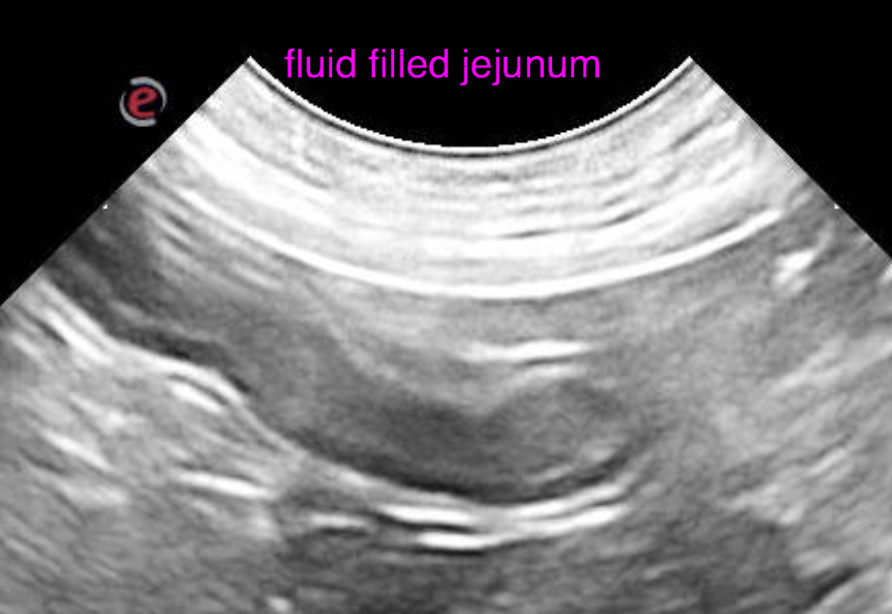

The left and right lobe of the pancreas are embedded in a slightly hyperechoic mesentery, but within normal limits for size, shape and echoarchitecture.  The gastric wall presents moderate generalized wall thickening emphasizing the submucosal layer. The interrugal wall thickness is up to 5 mm. The wall layering is moderately obscured. The mucosal surface is slightly irregular. A moderate amount of fluid is present within the stomach. The surrounding mesentery is mildly increased in echogenicity with slightly ill defined echotexture. The stomach is hypomotile. The duodenum is slightly dilated with fluid, presents hypermotility and mucosal fogging. The wall layering is witho normal limits. The jejunum presents similar changes as the duodenum. There is no obstructive pattern of the digestive tract.